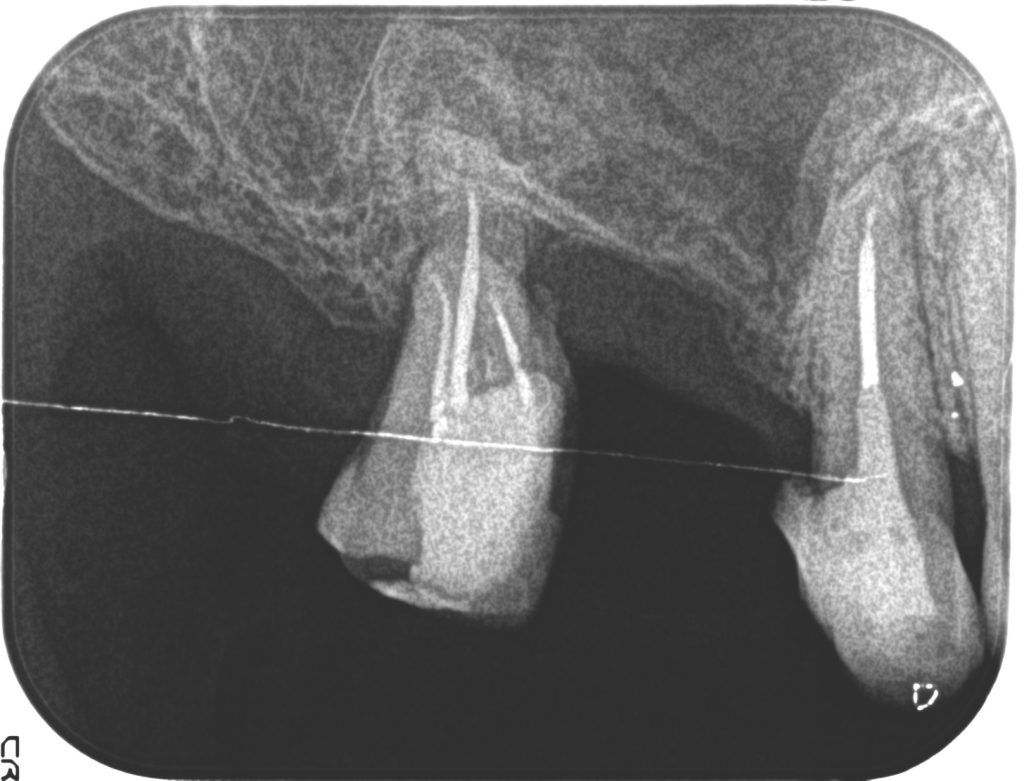

症例170代 男性 主訴 噛むと痛みがあり、しっかり噛めない

治療前

治療後

治療前

治療後

左下前・小臼歯部のブリッジによる荷重負担の為、隣在歯を守るインプラントを選択。

左下4番に単独インプラントを埋入。

オペ後、骨との密着値も良く、約2ヶ月後には、ジルコニアを装着し終了。

リスクとしては外科的侵襲がある。デメリットは、保険外診療の為、経済的負担がある。

費用 53万(税込)(オペ・仮歯・最終補綴物まで含む)